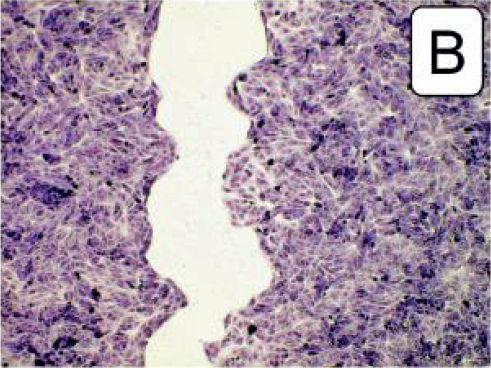

Untersuchung kultivierter Nierenzellen durch Prof. P. Dartsch** Ergebnis: schnellere Regeneration

**“Mikroskopische Darstellung der förderlichen Wirkung des Wasserstoffwassers von misterwater auf die Zellregeneration kultivierter Nierenzellen innerhalb von 12 Stunden. (A) Unbehandelte Kontrolle. (B) Reduzierter zellfreier Raum und damit bessere Zellregeneration durch Verwendung von 40 Vol% Wasserstoffwasser im Kulturmedium. (C) Größerer zellfreier Raum und damit schlechtere Zellregeneration durch Verwendung von 40 Vol% Stillem Wasser (= Ausgangswasser) im Kulturmedium. Fixierte und angefärbte Präparate im Olympus IX-50 Inversmikroskop mit 10x Planachromat und Olympus E-10 bei 4 Megapixeln Auflösung im Durchlicht-Hellfeld-Verfahren.“ (Prof. P. Dartsch, 20.06.2021: Förderliche Wirkeffekte des Wasserstoffwassers der misterwaterGmbH, Untersuchungen mit kultivierten Nierenzellen; verwendet wurde Wasserstoffwasser aus dem misterwater® Lourdes Generator)